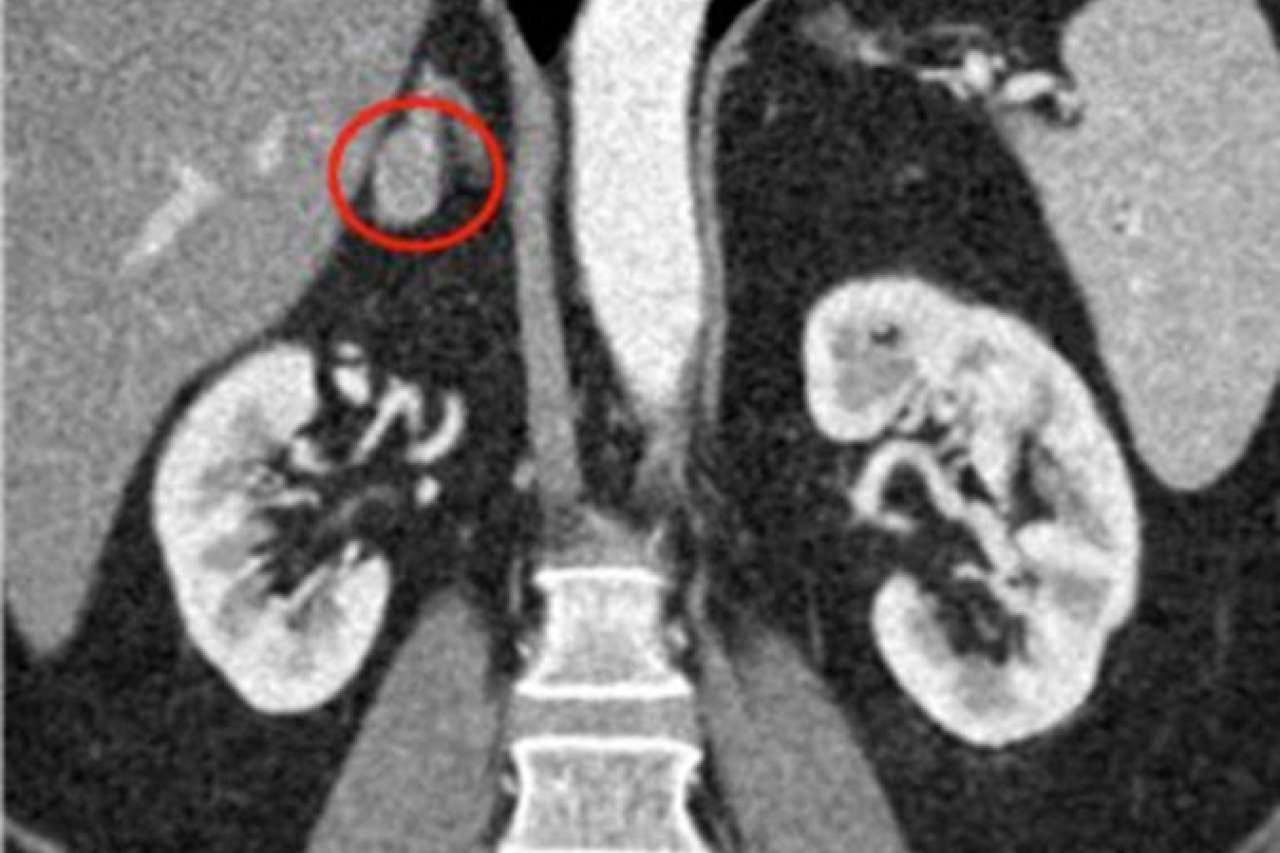

Red circles show small adrenal tumors.